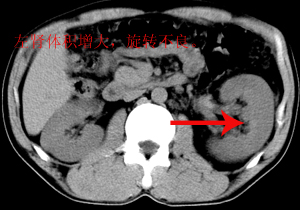

以下是引用andymaomao在2007-4-30 14:28:00的发言:[br]支持:1.慢性胰腺炎并假性囊肿形成可能;[br] 2.左肾形态稍增大,旋转不良。